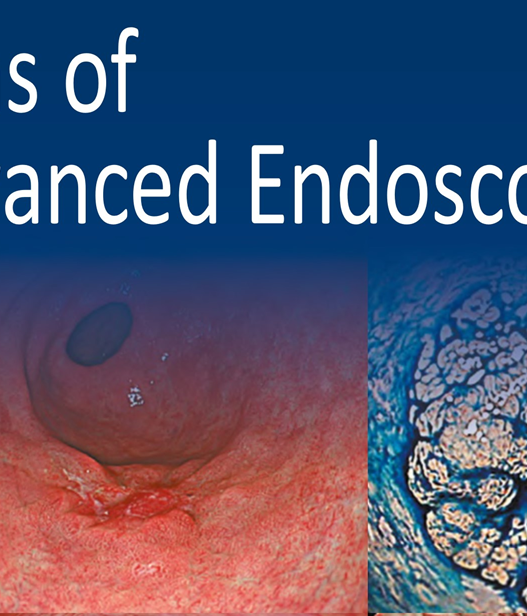

Since the introduction of this classification, several IEE techniques have become commercially available through advances in endoscopy technology, including blue light imaging (BLI), linked color imaging (LCI), red dichromatic imaging (RDI), and texture and color enhancement imaging (TXI). Therefore, a revised version including those techniques is presented in Fig. 1.

The LASEREO system (FUJIFILM Co., Tokyo, Japan) based on laser endoscopy was developed for advanced IEE, including WLI, BLI, and LCI. LCI using short-wavelength narrow band laser light combined with white laser light is a new technique that enhances differences in red coloration through digital processing [2]. This enables LCI to visualize red lesions better by enhancing their intensity relative to whitish lesions, which appear whiter. Recently, a controlled, multicenter trial with randomization using minimization has reported that LCI is more effective than WLI for detecting neoplastic lesions in the pharynx, esophagus, and stomach [3].

RDI is a type of novel IEE technology included in the EVIS X1 system launched by Olympus Co. in 2020. It is an imaging technique that enhances the contrast of deep tissue and blood vessels [4]. RDI has been reported to be useful for not only its initial development purpose, i.e., endoscopic hemostasis, but also other advanced interventions and even evaluation of inflammation activity. On the other hand, TXI developed by Olympus Co. is designed to enhance three image factors in WLI—texture, brightness, and color—to clearly define subtle tissue differences [5]. TXI is an innovative IEE that facilitates the adjustment of brightness and emphasizes surface irregularities and color differences in endoscopic images. As further data are accumulated, these new IEE technologies are expected to make a significant contribution to clinical practice.